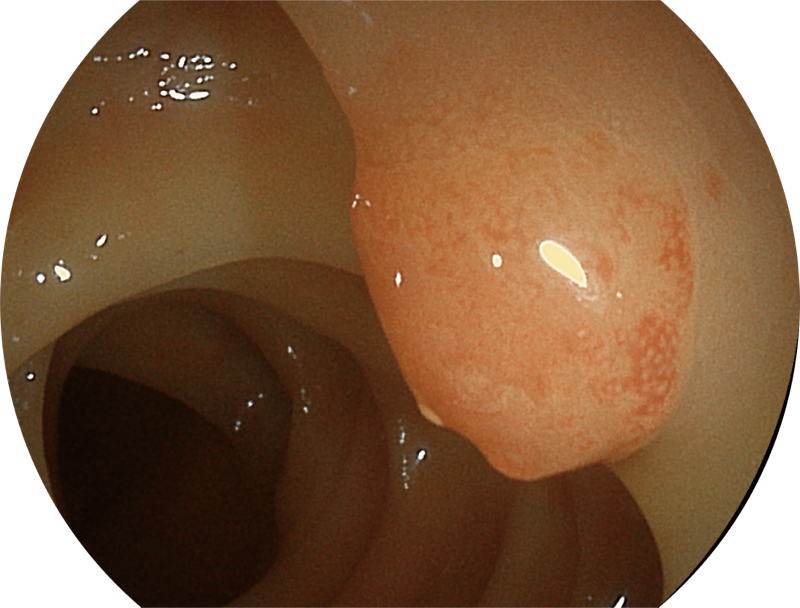

能够凸显黏膜浅层血管轮廓和黏膜表面微结构,适用于中、近景观察下的早癌精确诊断。